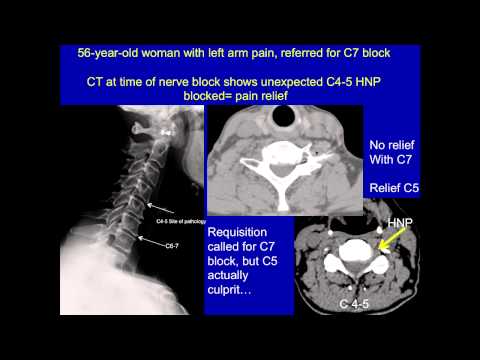

UCSF Radiologist Dr Dillon: Understanding how CT Scanners can help pin point other causes of lower back pain for a more precise diagnosis. CT allows opportunity to visualize other causes of pain at time of injection. Integration of history, physical examination and imaging is a very powerful tool. Doctors would see the patient, examine the patient, scan the patient, and

Visualizing Other Causes of Back Pain | UCSF Radiology